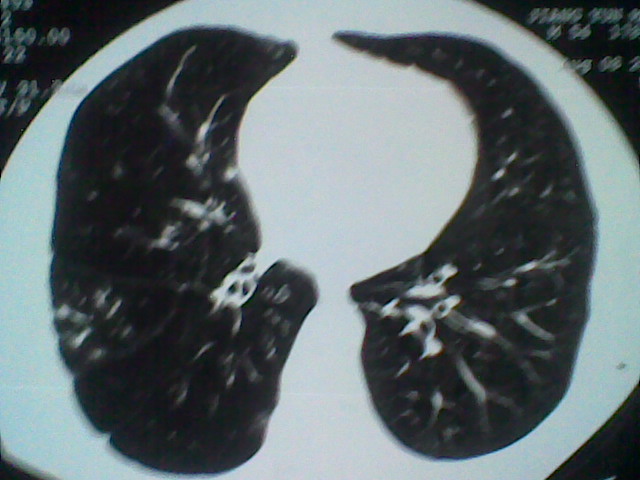

标题: CT21512:支扩伴感染?

患者女。咳嗽数天,咯血半天。

我们报的是支扩伴感染?

支持楼主意见,还有肺气肿